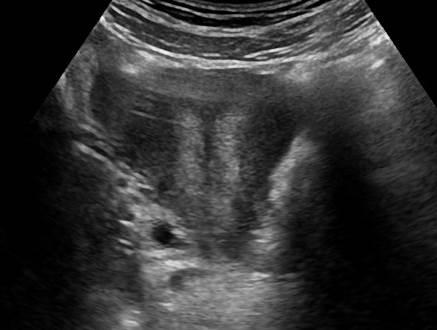

Dị dạng tử cung

» Thông tin: Nữ giới – 14 tuổi.

» Lâm sàng: Kiểm tra sức khỏe.

# Tử cung có vách ngăn (Septate uterus).